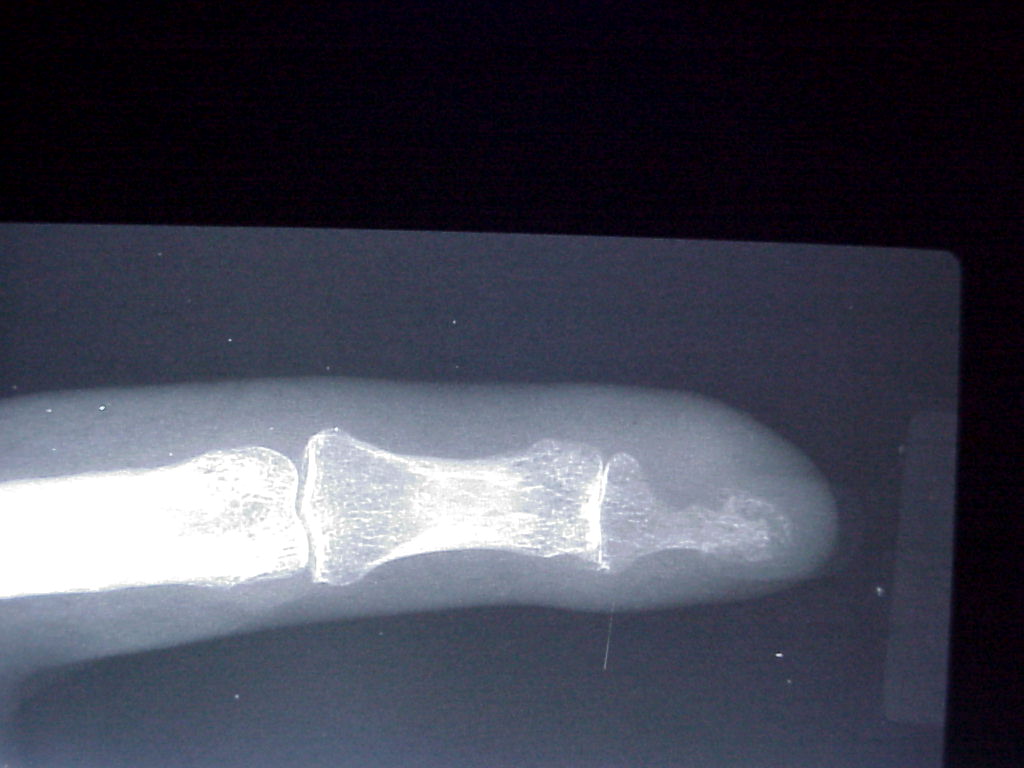

Breast cancer is known to metastasize widely. This patient with poorly differentiated breast cancer developed a fingertip mass. Biopsy confirmed metastasis, but she declined further surgery.

Probable erosive changes of adjacent distal phalanx.